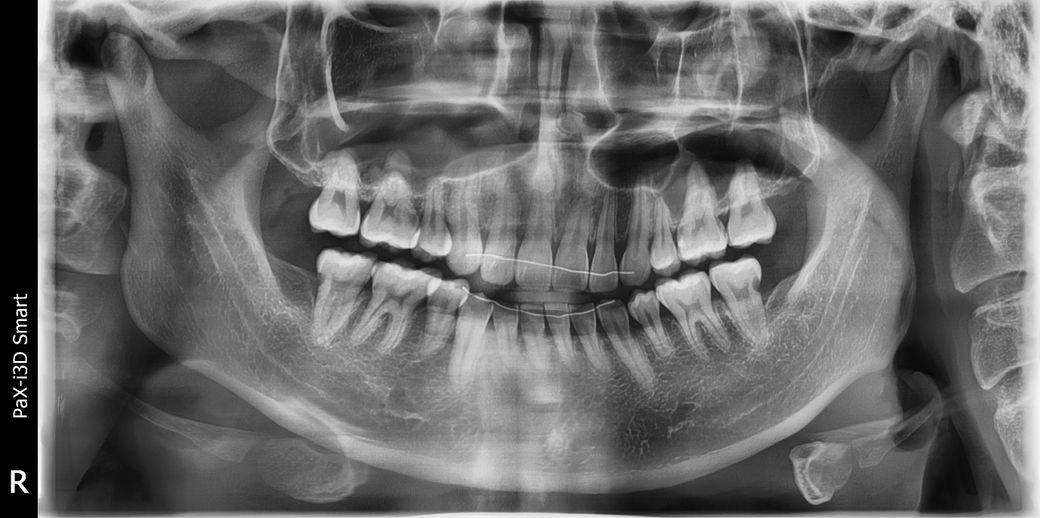

충치 갯수는 몇개인가요??????

같은 파노라마 사진으로 다른 질문을 드려요!

사진상 충치는 정확히 2개 맞을까요?

아랫니 양쪽 끝 1개씩이요

혹시 더 있다면 알려주시면 감사드리겠습니다 ㅠ

충치가 몇개 관찰이 되지만 파노라마 사진 한장만으로 충치를 진단해드리기는 어렵습니다.

아래 양쪽 젤 뒤 어금니 뒤쪽에 충치가 잇는거 같습니다 불편하시면 치료를 하시는게 좋을것같습니다.

파노라마 사진상 보이는 충치는 양쪽 아래 맨끝 어금니 2개 뒷면이고요 사진상 왼쪽 위 첫번째 큰 어금니 옆면도 충치가 의심되나 정확한건 작은 치근단 사진을 찍어봐야합니다